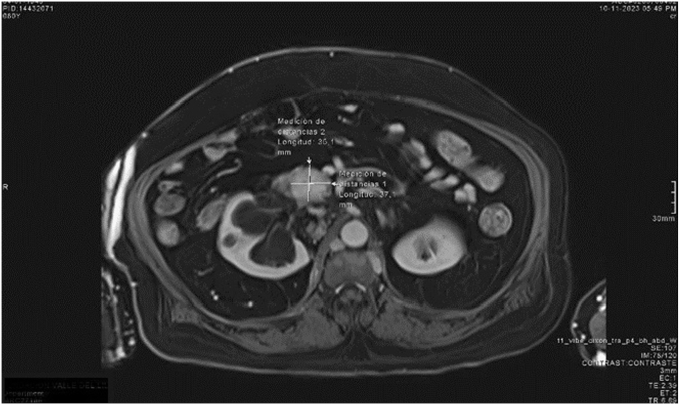

We describe the case of an elderly male patient with multiple comorbidities and recurrent isolated insulinoma of 3.7 × 3.5 cm involving the uncinate process of the pancreas and contacting the splenomesenteric confluent many years after first resection, in whom, after refusing surgical management, was performed as successful arterial embolization of the pancreatic tumor.